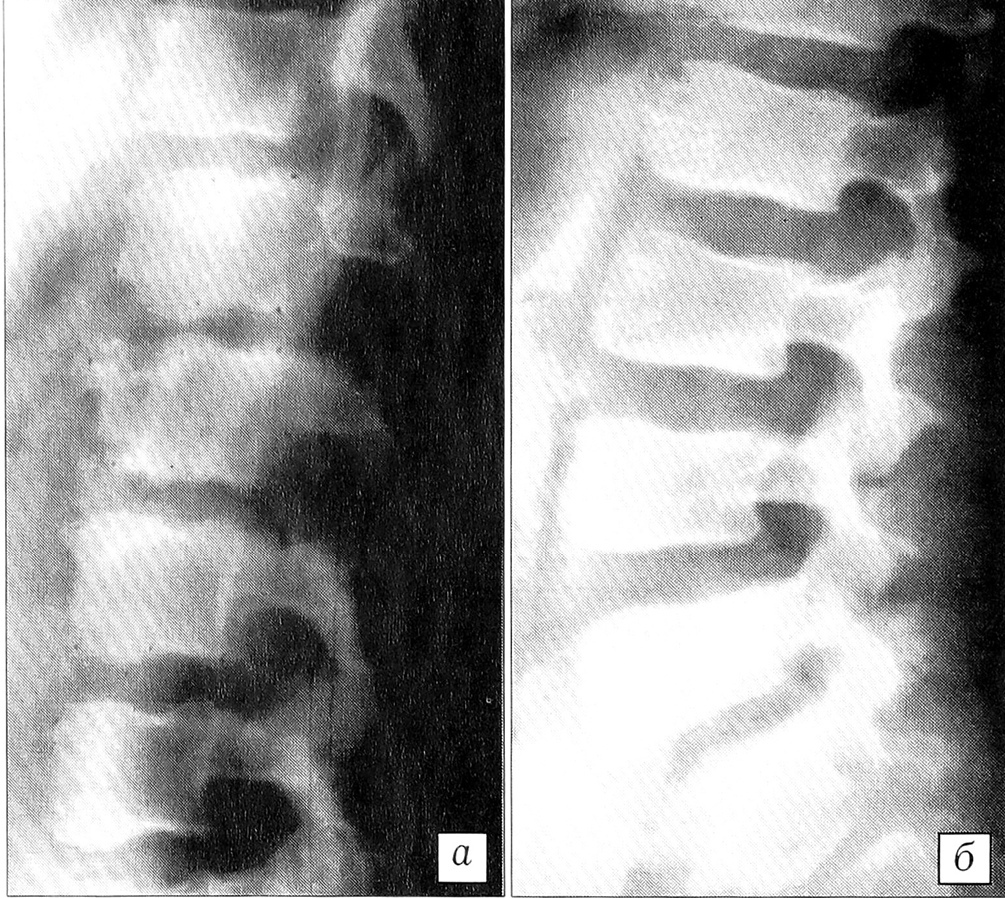

Рис. 5. Рентгенограммы (а — прямая, б — боковая) поясничного отдела позвоночника больного М. 16 лет. Остеохондропатия в сегментах L2-3, L3-4; уменьшение высоты L2~3, L3_4 межпозвонковых дисков, спондилоартроз.

Структурная недостаточность замыкательных пластинок и снижение механической жесткости губчатой кости тела позвонка вследствие остеопороза нарушают метаболизм межпозвонкового диска, что влечет за собой дистрофию его тканей. Дистрофические изменения элементов межпозвонкового диска сопровождаются уменьшением его высоты и, соответственно, дислокацией суставных отростков. Площадь контакта между суставными фасетками увеличивается, и в этих условиях они начинают воспринимать несвойственные им аксиальные нагрузки. Нарушение нагружения суставных фасеток вызывает изменение ультраструктуры и трофики суставного хряща с развитием спондилоартроза (рис. 5).

Последующие стадии патологического процесса характеризуются соответственно развитием спондилоартроза с гиперпластической деформацией суставных отростков и дуг позвонков (рис. 8) и формированием дегенеративного стеноза позвоночного канала. В дальнейшем, по мере нарастания дистрофических изменений в тканях диска, происходит компенсаторная перестройка губчатой кости тела позвонка: более равномерное восприятие компрессионных нагрузок над всей площадью диска с отсутствием физиологического прогиба замыкательной пластинки сопровождается изменением жесткости трабекулярной кости [18] с появлением участков анизотропии — локального остеопороза и локальной гиперплазии (рис. 9).